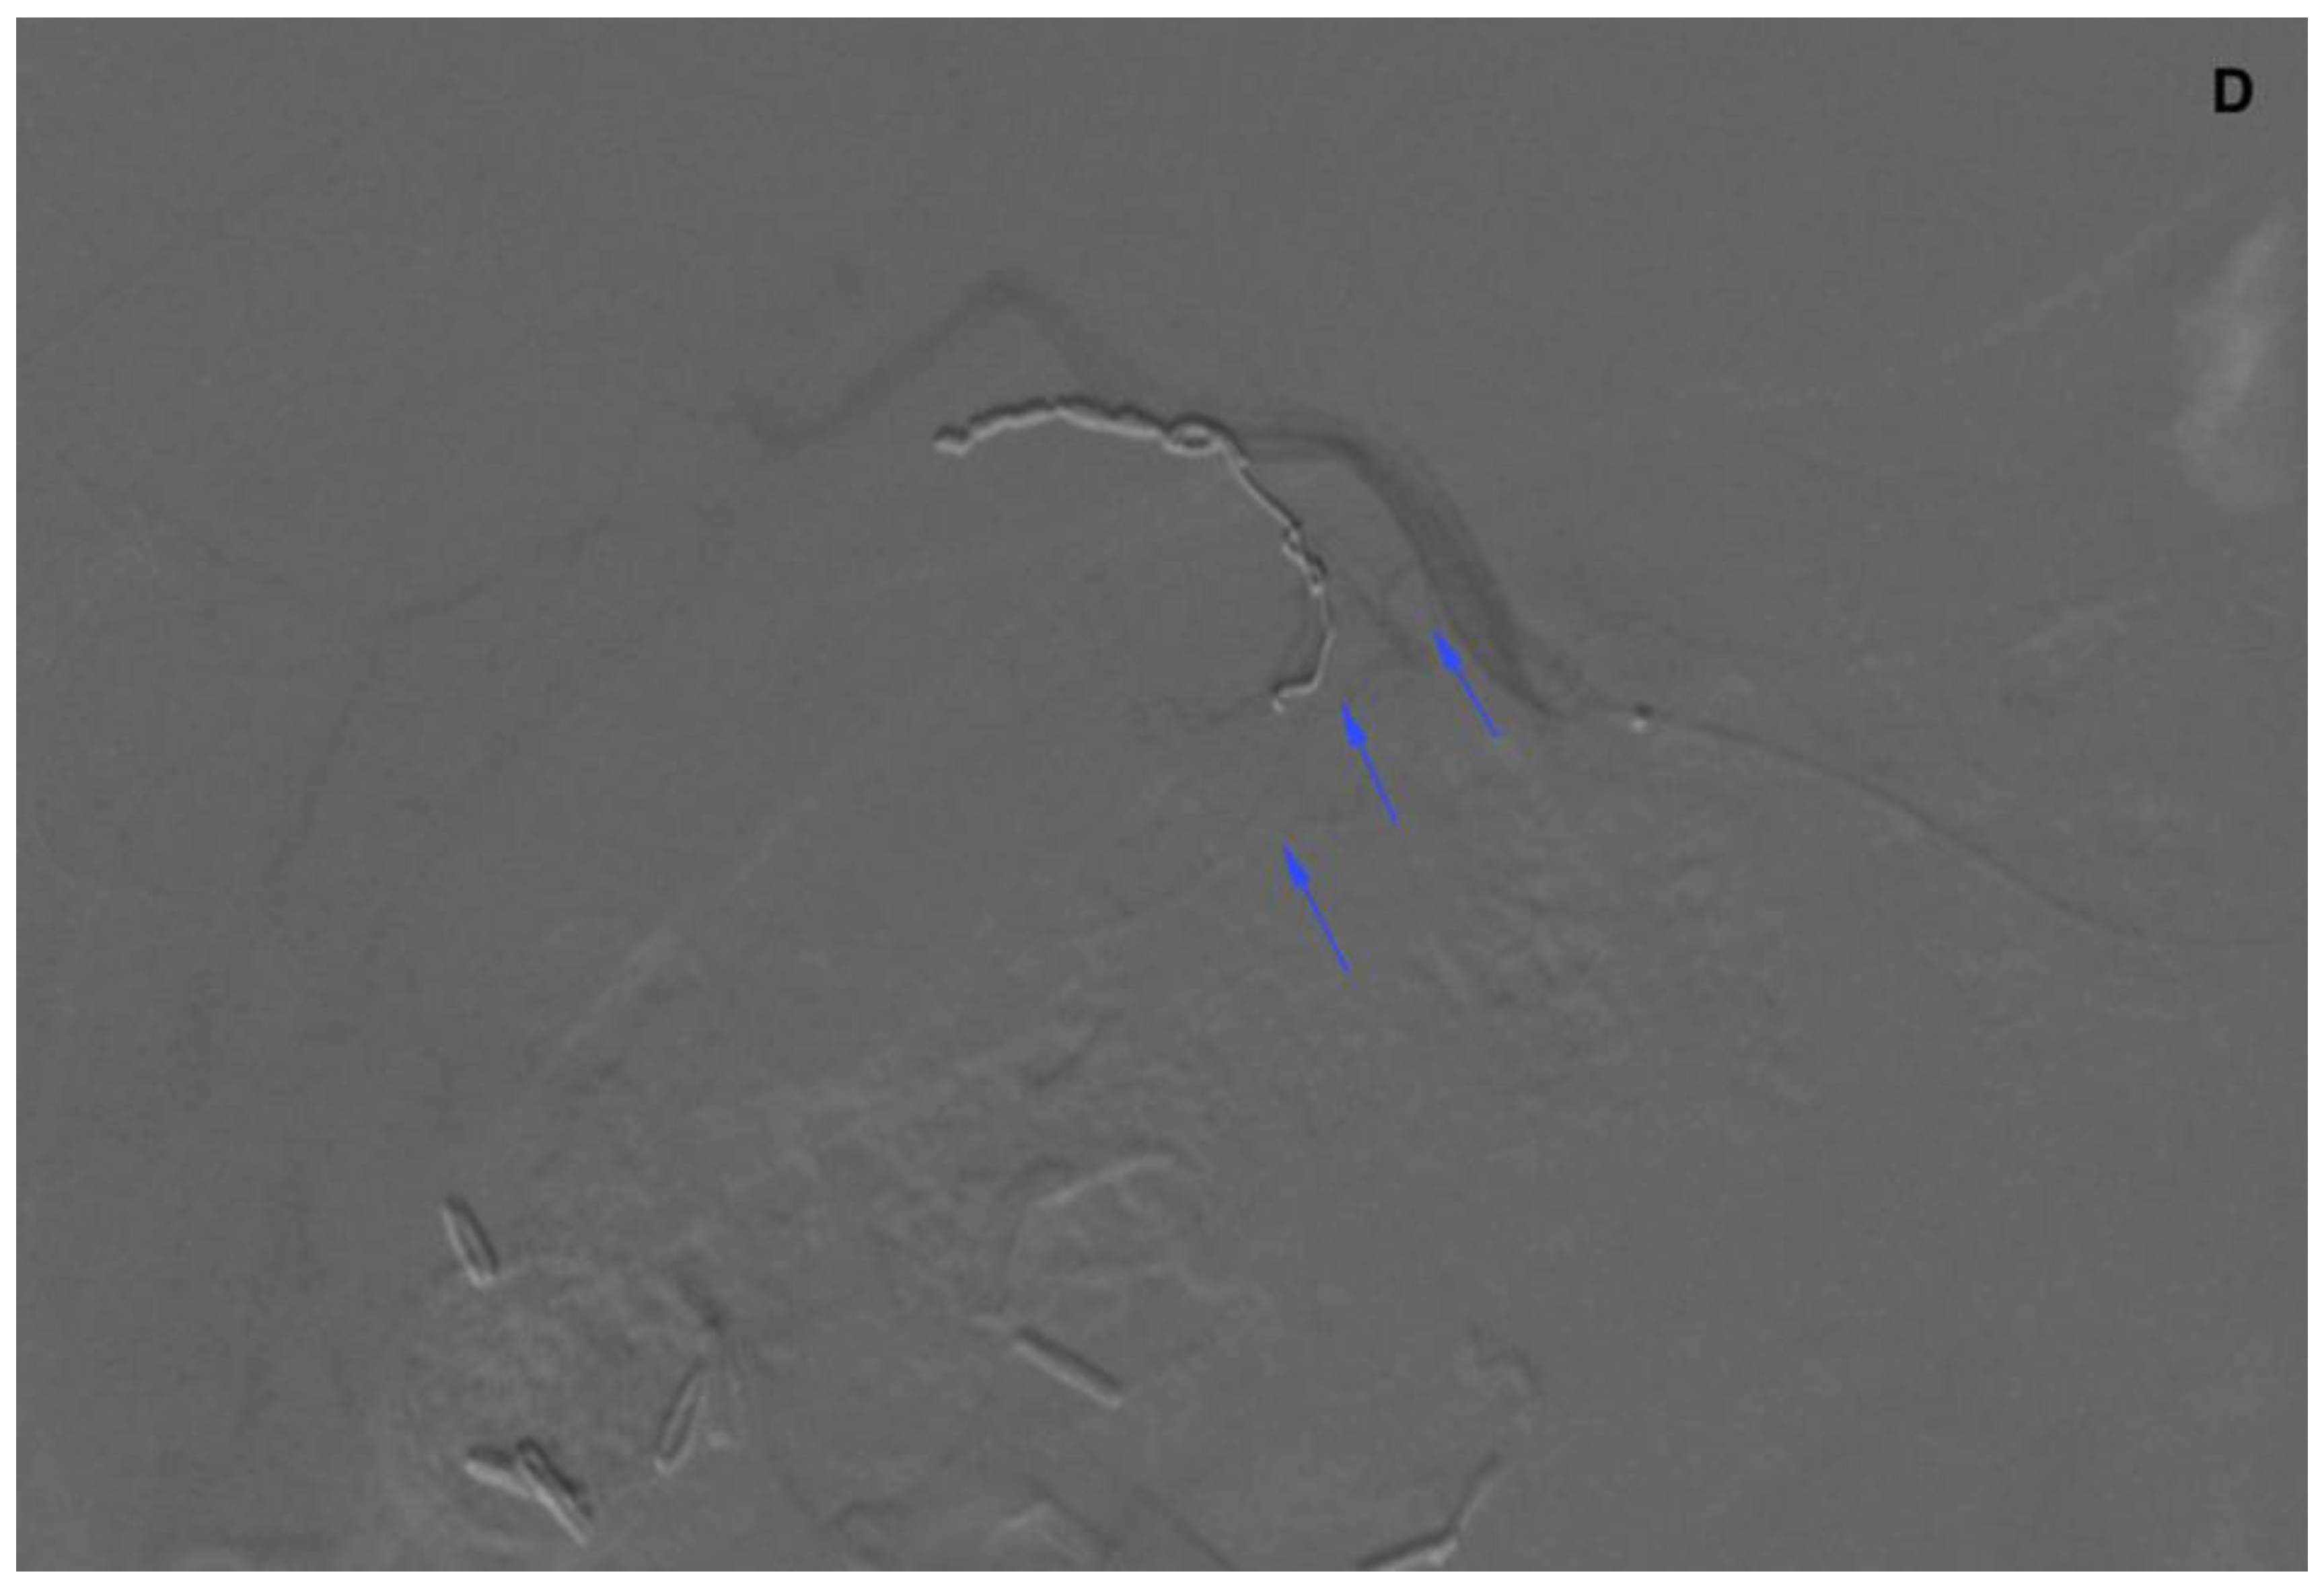

Figure 3.

Angiogram of the right hepatic artery. (A) Initially, single CA is visible (arrows) originating from the right hepatic artery division. (B) After embolization, another artery reveals multiple intrahepatic anastomoses to the gallbladder wall, and needs to be embolized. (C) There is insufficient embolization of both CA, and (D) retraction of the microcatheter reveals another CA originating proximally to the right hepatic artery division (arrows).